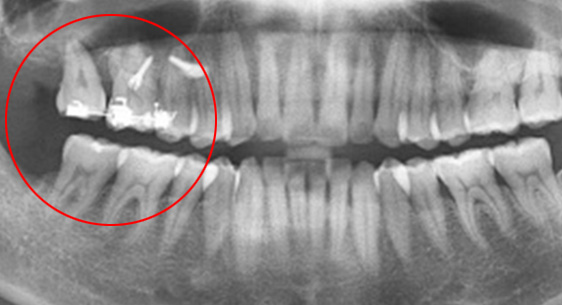

치조골 손상이 심해 발치를 하고 임플란트를 해야 하는 상황

인접치아로 발치된 공간을 메움

30대 남환으로 다른 치과에서 임플란트 5개 진단을 받고 내원. 교정과 협진으로 공간을 메꾸고 오른쪽 위 치아에 임플란트를

1개만 식립하여 자연치아를 최대한 활용하는 진료 계획을 세움.